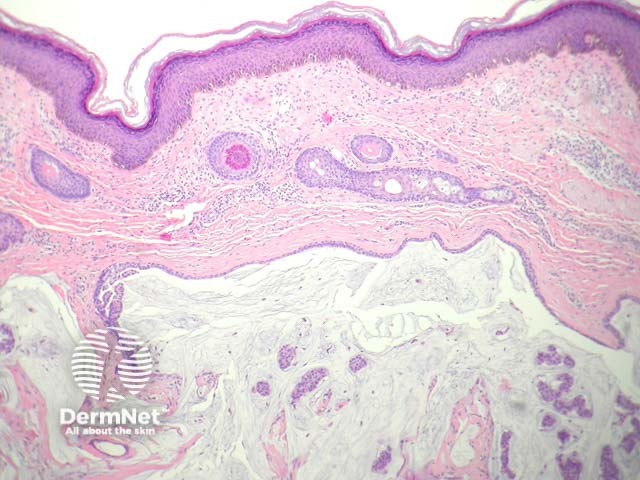

In mucinous carcinoma, there is a dermal mass composed of glands and solid nests of epithelial cells which appear to be floating in copious mucin (figures 1–3). The cells are enlarged, show mild pleomorphism and often have an eosinophilic cytoplasm (figure 3).

Figure 1